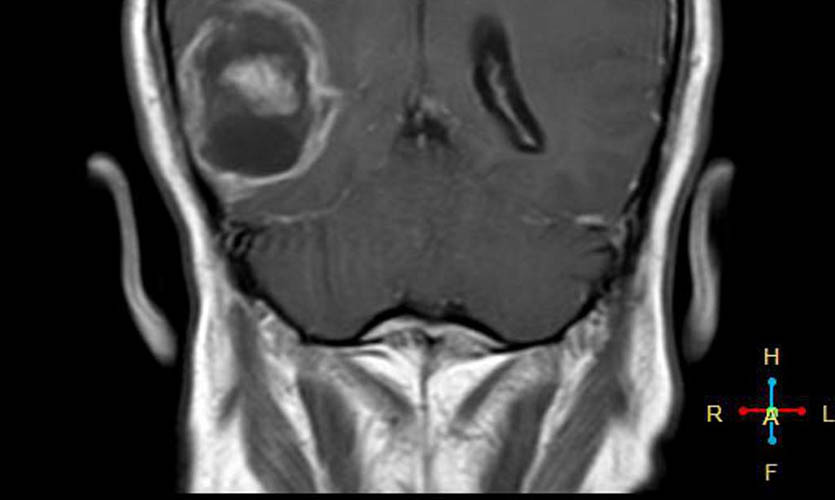

Но вот, частота опухолей височной доли увеличилась в период с 1998 по 2007 год. То есть во время широкого распространения мобильных телефонов среди населения.

Было проведено исследование радиочастотных электромагнитных полей путём оценки общей кумулятивной дозы удельной энергии (TCSE) для каждого человека. Для каждого случая местоположение опухоли определяли нейрорадиологами, а центр опухоли оценивался компьютерным алгоритмом или непосредственно нейрорадиологом.

Для каждого случая средняя точка опухоли на трехмерной сетке определялась на основе радиологических изображений.

По итогам исследования выяснялось, что у пользователей мобильных телефонов наблюдалось повышение шансов появления злокачественных опухолей головного мозга и развития астроцитомы при использовании мобильных телефонов только с одной стороны головы.

Проще говоря, если ваш смартфон лежит ночью с правой стороны (по статистике именно так), то риск появления опухоли возрастает именно справа.